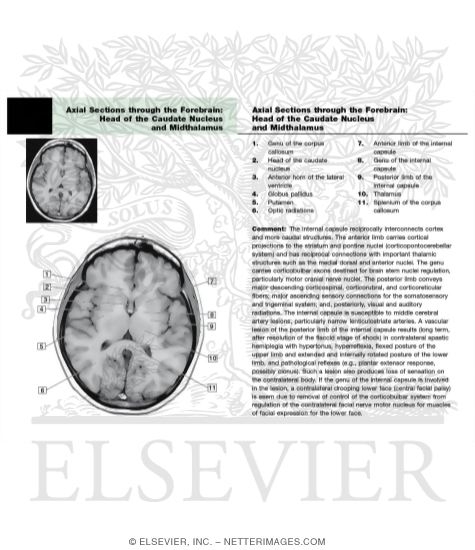

Axial Sections through the Forebrain: Basal Ganglia and Internal Capsule